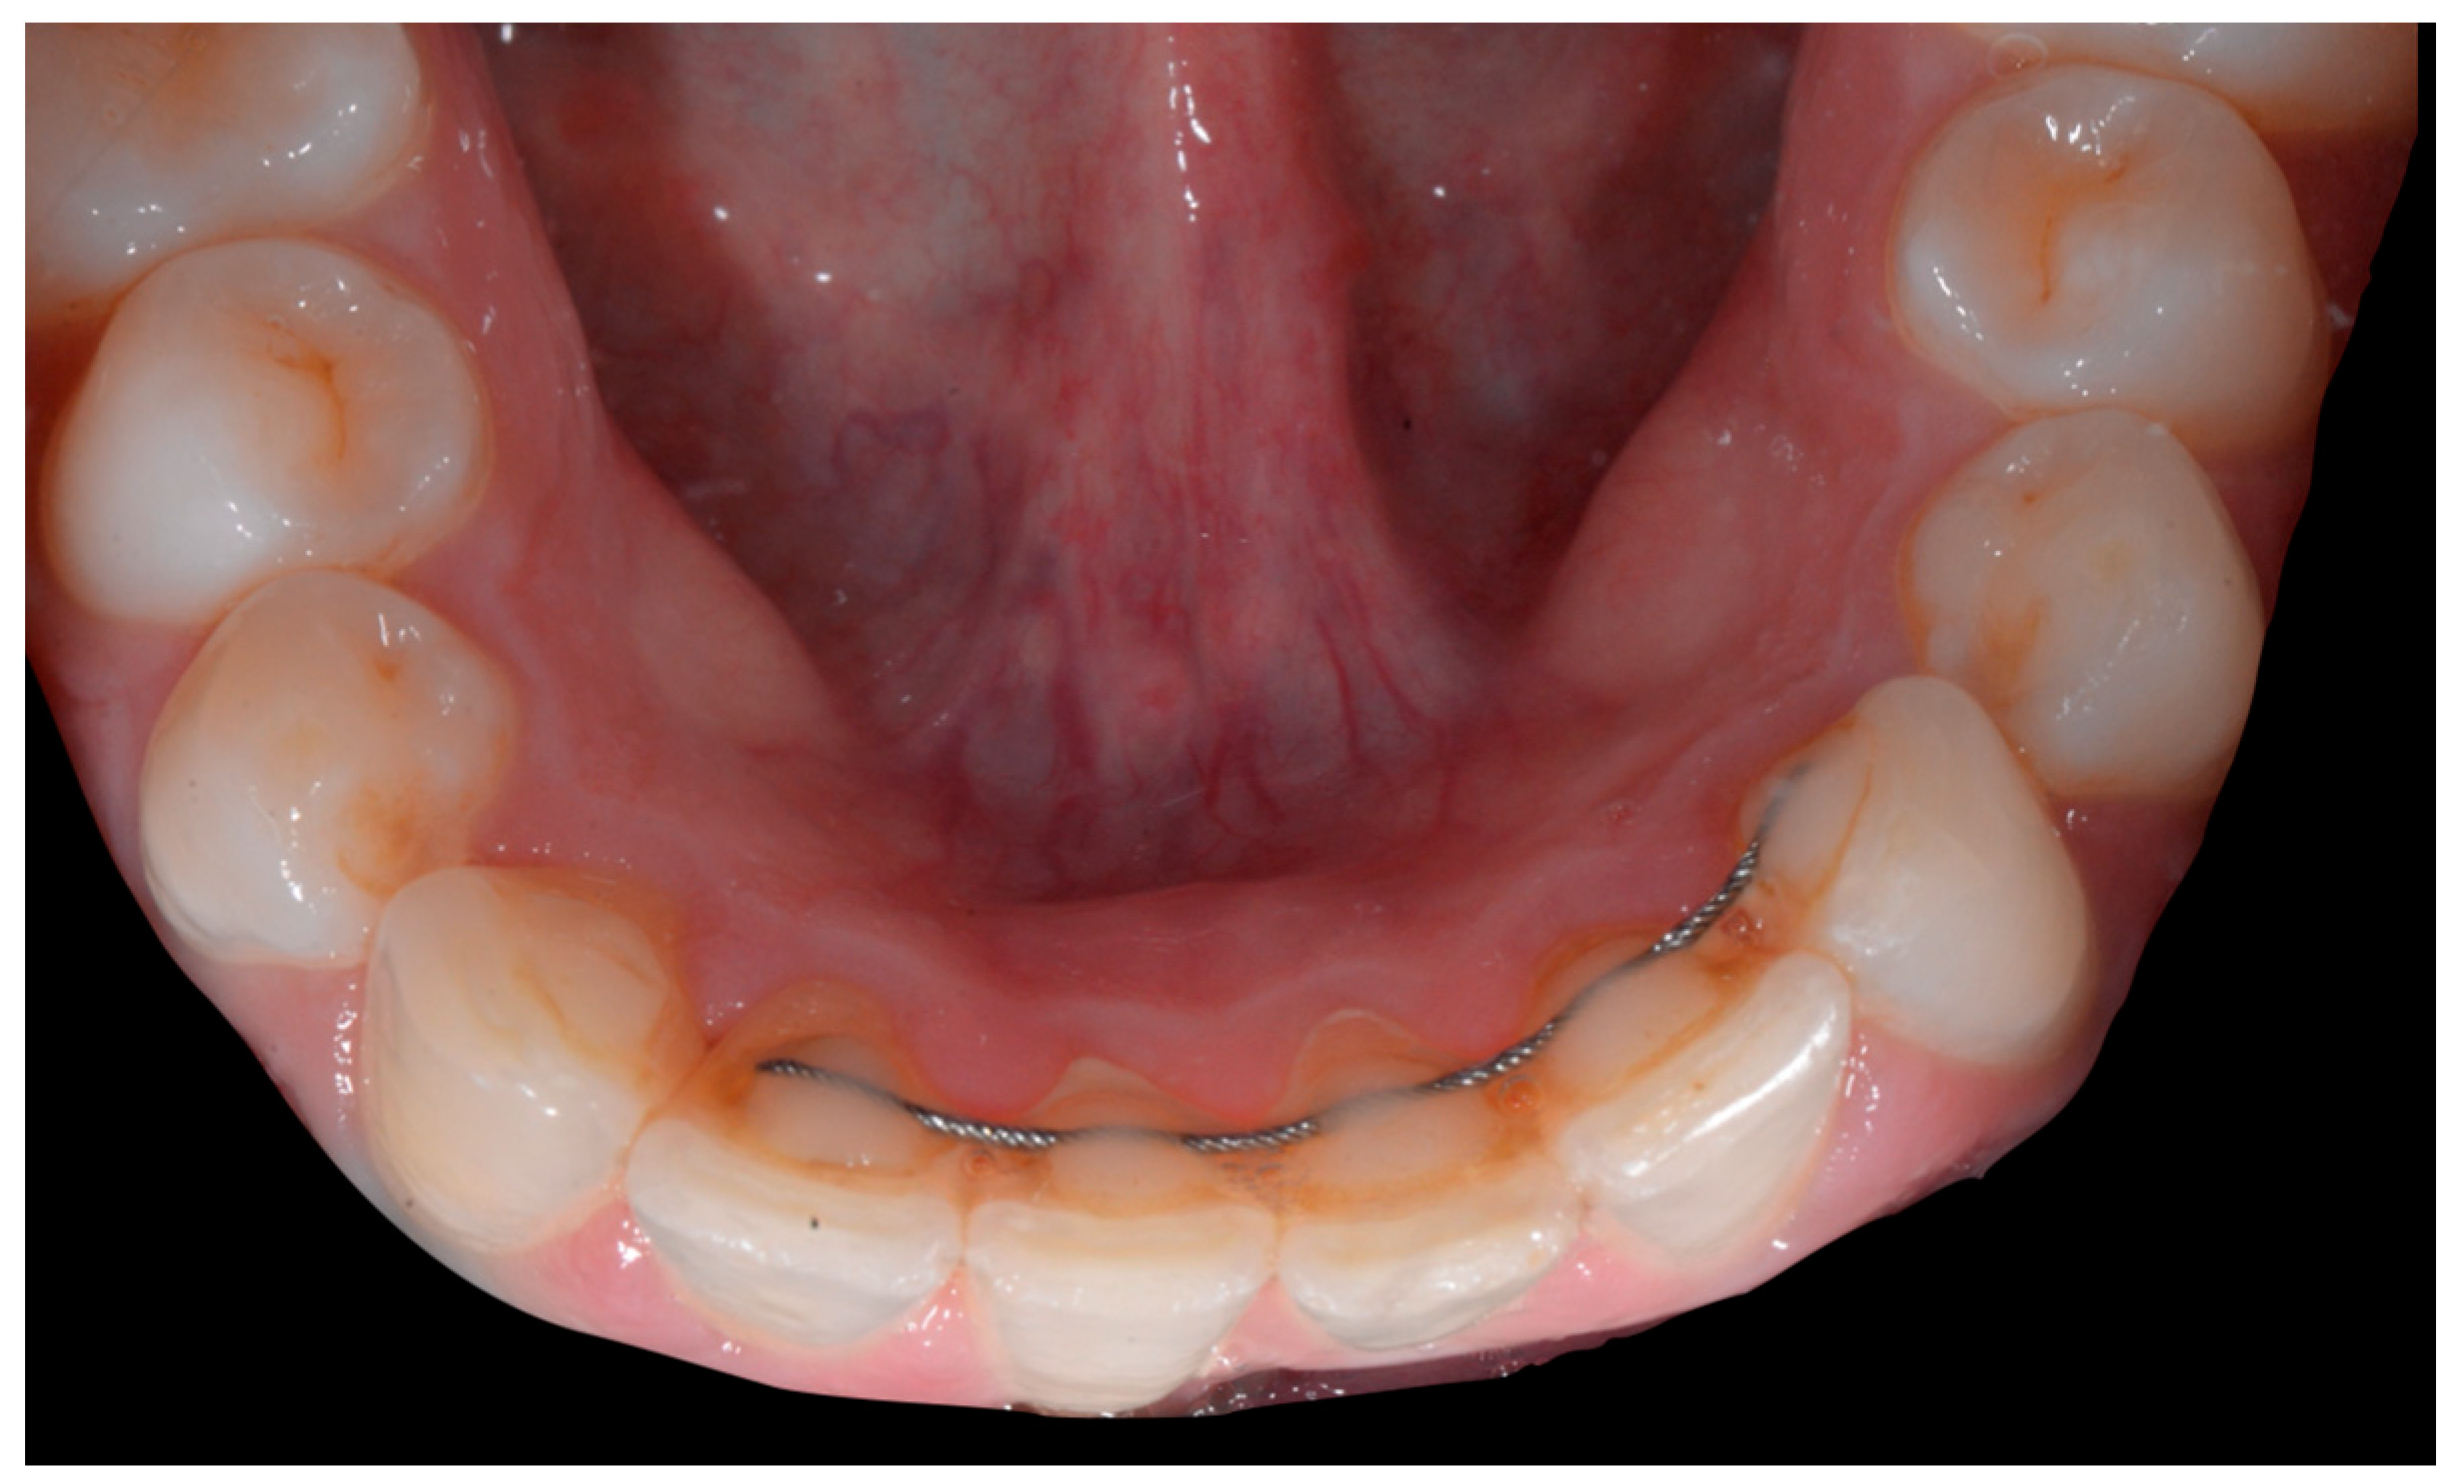

In the mandible, the retainer was broken distal to 42 and, despite being intact on 33, this tooth had increased visibility of its vestibular surface compared to its contralateral tooth (differential torque). Finally, teeth 31 and 41 also showed a difference in the visibility of their vestibular surfaces (differential torque). Ultimately, the patient was diagnosed with an X-effect wire syndrome on 21, an X-effect wire syndrome on 41, and a Twist-effect wire syndrome on 33.

No retainer was present in the maxilla, only a residual mandibular retainer, still bonded to 32 and 42, was visible (Figure 14), as well as incisal crowding and a difference in the visibility of the buccal and root surfaces of 41 compared to the contralaterals. In this extreme clinical situation, a severe and terminal wire syndrome on tooth 41, the “X-effect” type, was observed.

Figure 14.

Severe wire syndrome. Occlusal view.